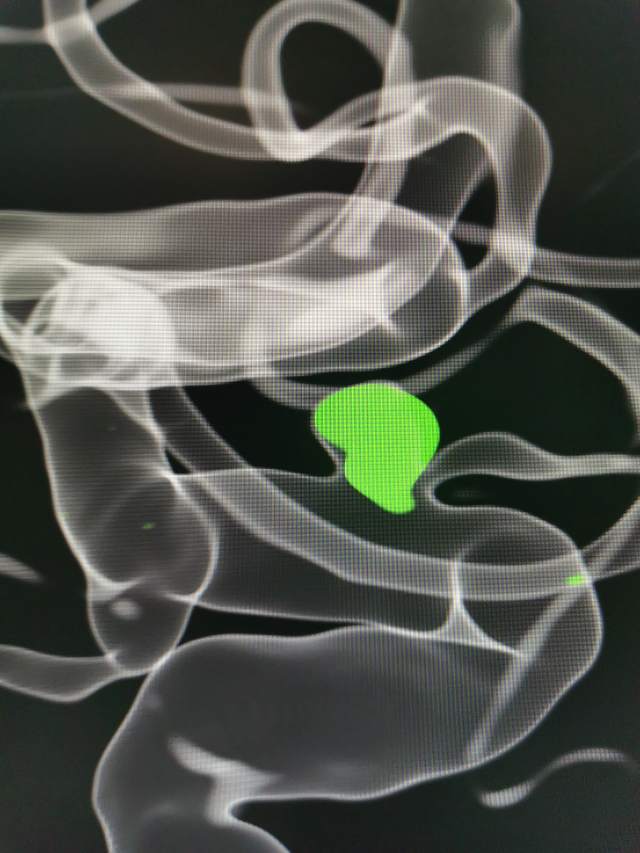

44岁盐城帅哥,因“头痛3天”发现静脉窦血栓合并“颅内动脉瘤“来诊。颅内动脉瘤之一是瘤体累及眼动脉的相对宽颈微小动脉瘤(2.5mm),此部位动脉瘤存在破裂出血的风险,而且静脉窦血栓的治疗也会加重此风险,有必要同步先消除这个潜在的风险。病变累及眼动脉,如果治疗过程中受到累及存在失明风险,需要重点保护。最终,采用一个支架一个圈的“简约模式:花费少,效果好”结束手术,眼动脉保留良好。